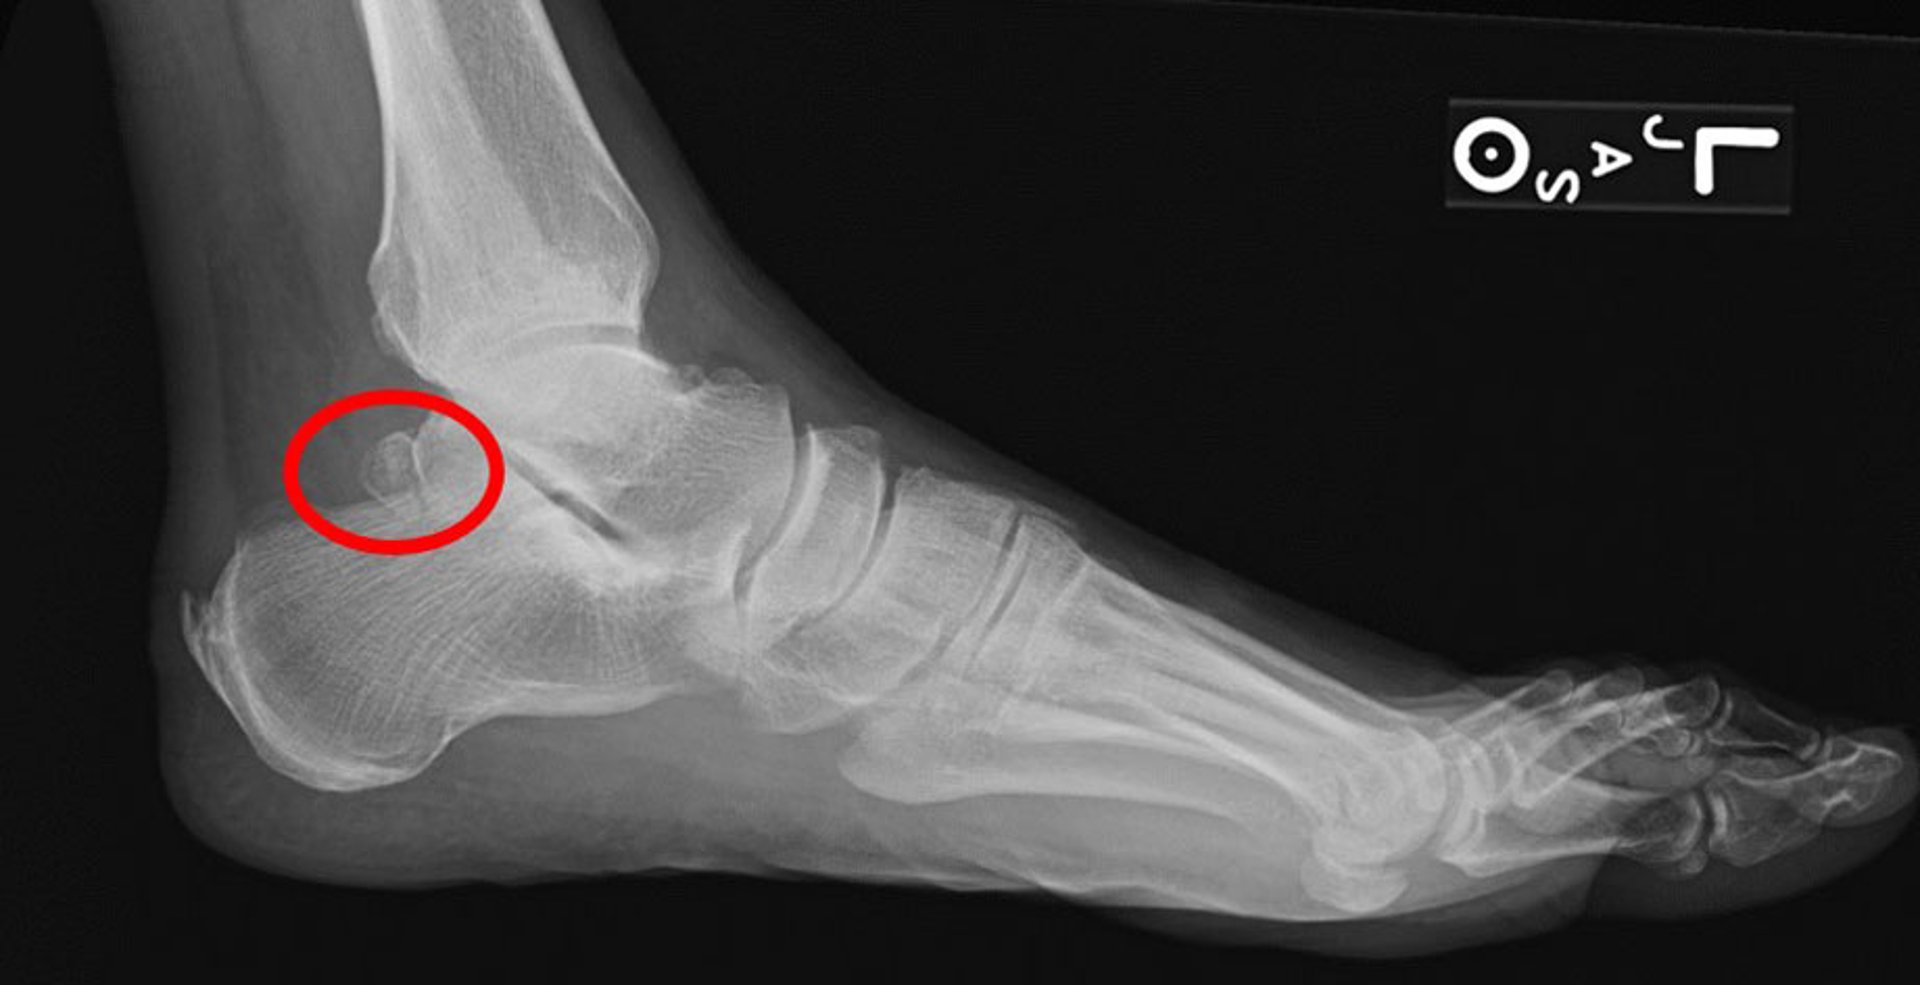

Os trigonum syndrome

Os trigonum syndrome commonly presents with posterior ankle pain that can mimic symptoms of Achilles tendon disorders such as retrocalcaneal bursitis. It is the result of a partial or incompletely fused accessory ossicle located adjacent to the flexor hallucis longus (FHL) tendon as it crosses the subtalar joint at the posterior aspect of the talus and superior to the calcaneus. The presence of an os trigonum does not always equate to a painful syndrome. However, in patients who develop posterior ankle pain in the setting of repetitive stress related to hallux plantarflexion (eg, a ballerina dancing "en pointe" or in forced ankle plantarflexion), os trigonum syndrome should be considered.

Fracture of the posterolateral talar tubercle usually causes tenderness anterior to the insertion of the Achilles tendon. Bursitis is often differentiated from the fracture by the localization of warmth and swelling contiguous to the tendon and pain localized primarily in the soft tissue. Also, using the thumb and index finger, compressing side-to-side anterior to the Achilles tendon causes pain. The presence of a symptomatic os trigonum, an accessory ossicle, is included in the differential diagnosis, as well as flexor hallucis longus tendinopathy (1).

Radiographs are taken to exclude fracture and to reveal erosive calcaneal changes characteristic of chronic rheumatoid arthritis, gout, or spondyloarthropathies. Magnetic resonance imaging (MRI) of the Achilles tendon can confirm the presence of bursitis and exclude alternative diagnoses such as partial or full tendon rupture as well as calcaneal stress fracture. MRI is also helpful to distinguish between a posterior talar process fracture and os trigonum syndrome.